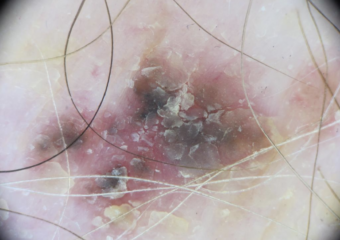

Actinic Keratosis (AK) Photos

Actinic keratosis on head or neck. Photo: International Skin Imaging Collaboration at isic-archive.com

Actinic keratosis on posterior torso. Photo: International Skin Imaging Collaboration at isic-archive.com